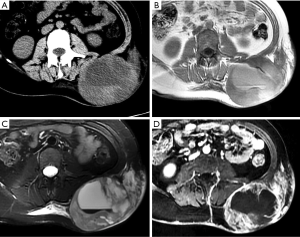

Endometriosis

The anterior abdominal wall is the most common site of extrapelvic endometriosis, which usually develops in a cesarean section scar, with a wide range of reported incidence rates of 0.03–3.5% (60). The most plausible cause of scar endometriosis is implantation of endometrial stem cells at the surgical site at the time of uterine surgery. Anterior wall endometriosis in patients with no prior surgeries is rare (61). Abdominal wall endometriomas are often the only manifestation of endometriosis with no associated pelvic endometriosis. The typical presentation is a female patient with cyclical pain from a mass in scar tissue (62).

The appearance of abdominal wall endometriosis on CT and MRI depends on the phase of the patient’s menstrual cycle, the chronicity of the process, the number of stromal and glandular elements, and the amounts of bleeding and associated inflammation (63). On CT, anterior abdominal wall endometriosis typically appears as a solid soft tissue mass that is hyperattenuated compared with muscle, although the attenuation can vary and be nonspecific. On MRI, it typically presents as a solid mass that is mildly hyperintense on both T1WI and T2WI as a result of subacute hemorrhage within the endometriotic crypts, although this finding may also vary (Figure 13). Mild to moderate contrast enhancement is present (60).